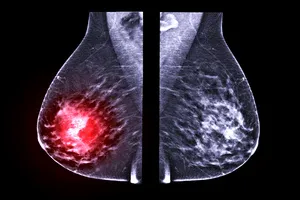

유방 결절은 다양한 원인으로 발생하며, 대부분 양성이지만 일부는 악성일 수 있습니다. 조직검사는 결절의 일부를 채취하여 현미경으로 분석하는 검사입니다.

이를 통해 결절이 양성인지 악성인지, 악성일 경우 어떤 종류의 암인지 정확하게 판단할 수 있습니다. 유방암은 조기에 발견할수록 치료 효과가 좋습니다. 조직검사를 통해 유방암을 조기에 발견하면 완치율을 높일 수 있습니다.

암세포가 발견된 경우 악성으로 판정됩니다. 악성 종양으로 진단되면 암의 종류, 전이 여부 등을 확인하기 위한 추가적인 검사를 받아야 합니다.